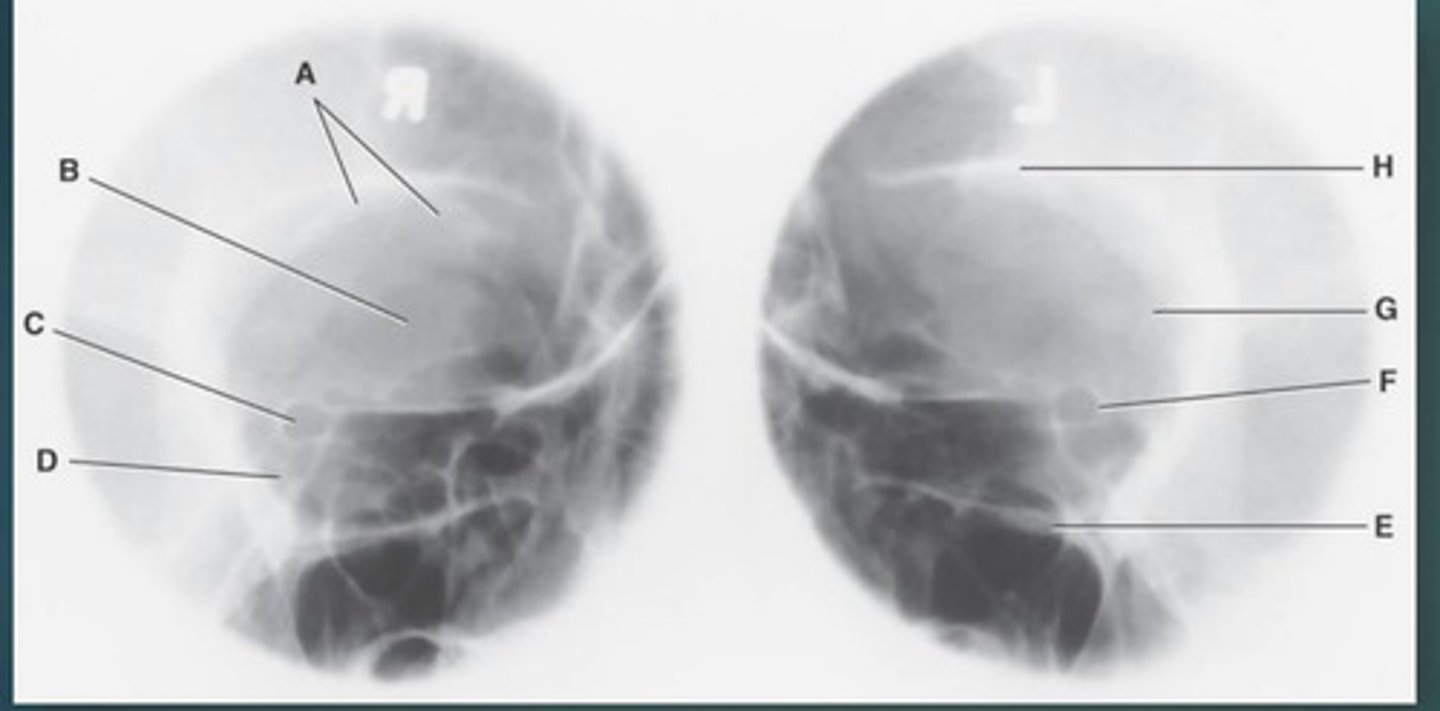

Lateral sinus

What position?

L. Orbital roofs

A.

L. Greater wings of sphenoid

B.

sella turcica of sphenoid

C.

L. Sphenoid sinus

D.

L. Rami of mandible

E.

L. Maxillary sinuses

F.

L. Ethmoid sinuses

G.

L. Frontal sinuses of frontal bone

H.